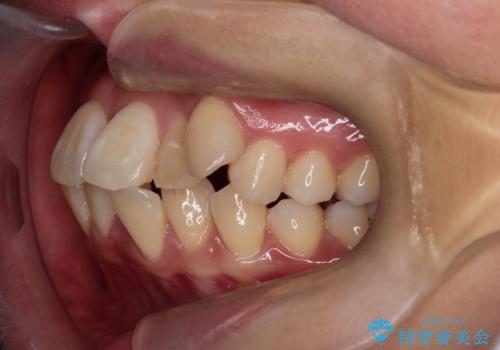

- 八重歯(叢生)と、上下の歯の中心線(正中)がずれていることを主訴にご来院されました。精密な検査の結果、歯列全体のスペースが大幅に不足しており、八重歯を正しい位置に配列し、正中のズレを改善するためには、上下左右の第一小臼歯を抜歯する必要があると診断。装置には、目立ちにくい審美ワイヤーを使用し、見た目を気にせず、機能性と審美性が完璧に整った咬み合わせを目指す治療計画を立案しました。

八重歯: 突出していた八重歯を歯列内に誘導し、デコボコを解消しました。

正中のズレ: 歯を左右対称に移動させることで、上下の歯の中心線を正確に合わせ、顔全体のバランスも改善しました。

治療の結果、長年気にされていた八重歯と正中のズレが解消し、機能的にも整った理想的な歯並びを獲得。目立たない装置で治療を完遂し、自信を持って笑える美しい笑顔を手に入れていただけました。